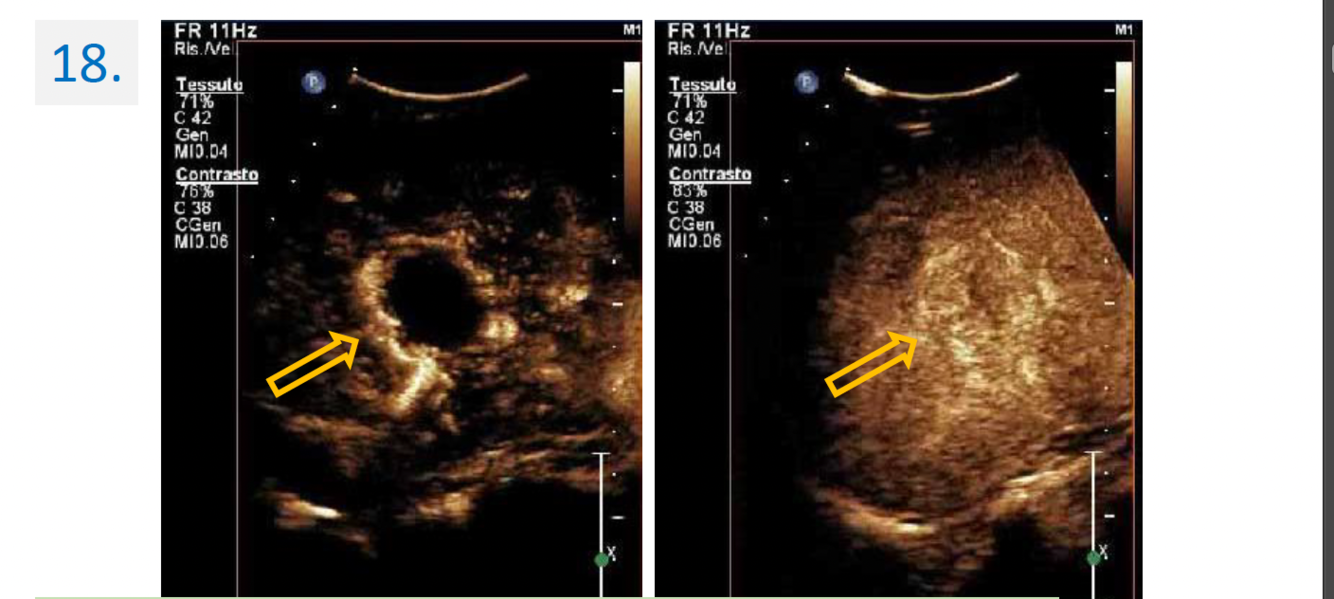

18

Region:

liver right subcostal view

Diagnosis:

Hepatic hemangioma